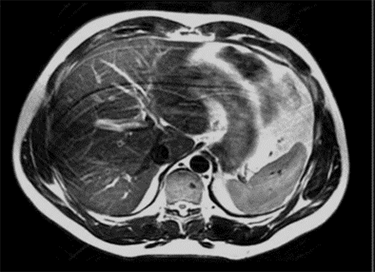

| Dielectric Effect Inhomogeneity/Shading in the image | ![]() | Interaction of matter with electrical component of RF field |